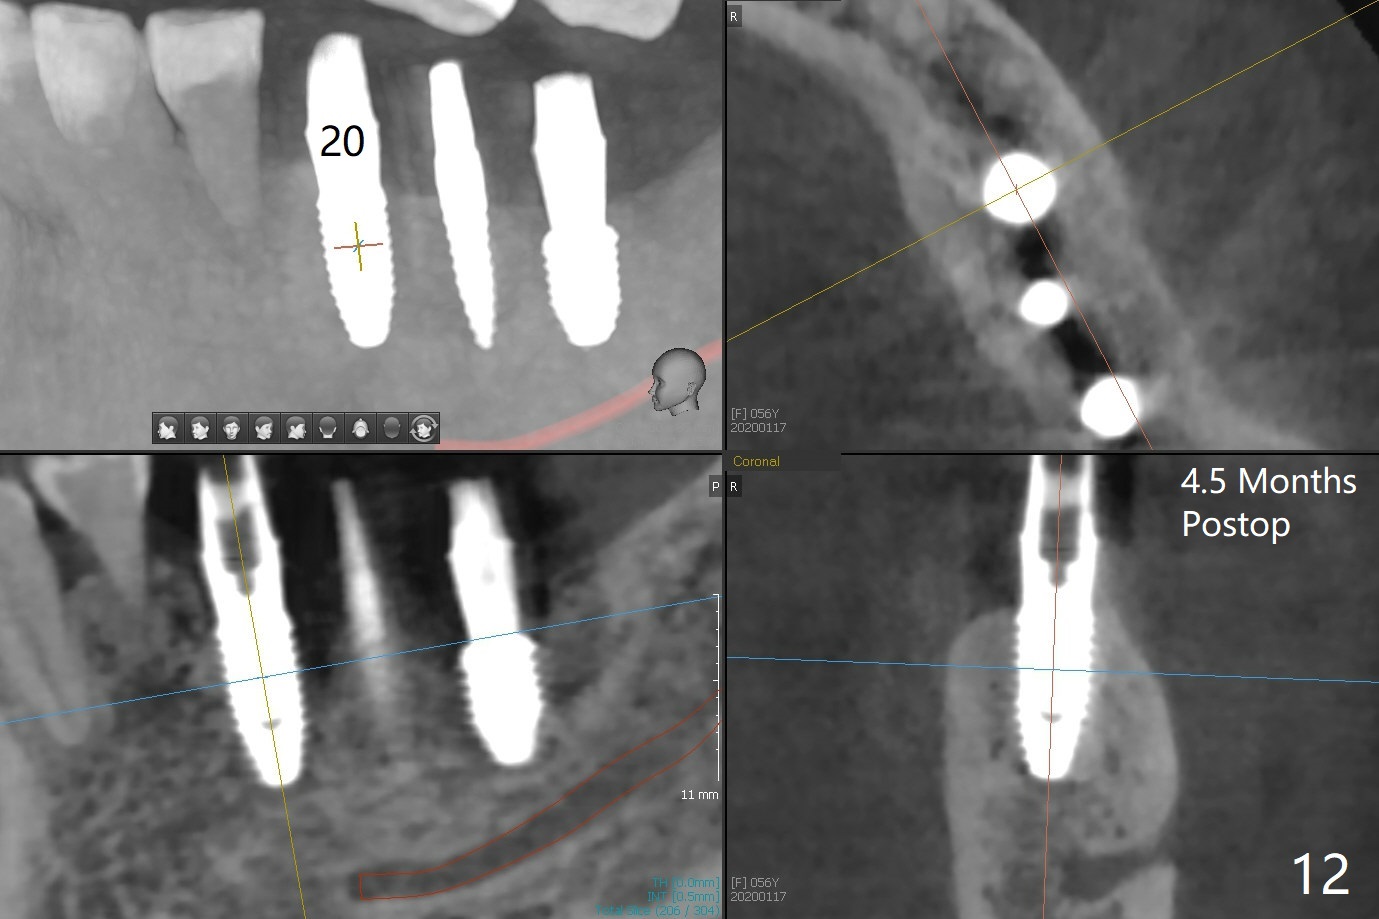

PA is taken after a 2.2 mm drill reaches the depth at #12, since osteotomy is initiated in the mesial slope of the socket (Fig.1 red dashed line) and the neighboring root (*) slightly curves distal. A 8.6x5 mm healing abutment is used to close the socket with the large mesiodistal space after bone graft (Fig.2 *). In contrast, the socket at #20 is large; a 4.5x4.5(3) mm cementation abutment is placed for an immediate provisional to keep autogenous bone (harvested from the site of #18) in place (Fig.3). Six months postop, the patient does not want implant FPD. She wants an additional implant at #19. Since the space between the implants #18 and 20 is 9.41 mm, a narrow implant is indicated (3 or 3.5 mm, Fig.4), in spite of the sufficient buccolingual width (Fig.5). The position and trajectory of the 1.2 mm initial drill and 3x10(2) mm 1-piece implant are acceptable with free hand (Fig.6,7). After 3-4 more turns, panoramic X-ray (Fig.8) and CT (Fig.9) are taken for 28-30 guide. It appears that the 1-piece implant is placed acceptable buccolingual (Fig.9 B). The implants at #12,18,20 (4.5 months postop with guide) are shown in Fig.10-12. It appears that guided surgery is superior in buccolingual position and trajectory to free hand. There is crestal remodeling without implant thread exposure 11 months postop (Fig.13).